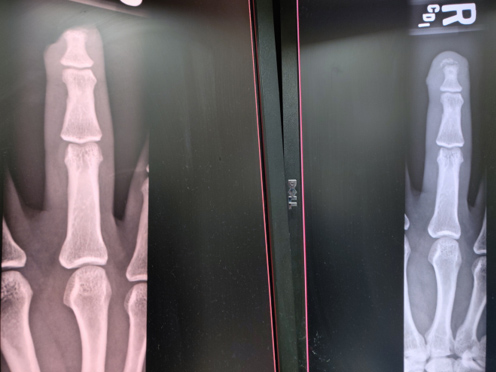

After reviewing the X-ray at bedside, emergency department physician proceeded with repair of the tissue. The amputation had left the nail intact as you can see on the lateral X-ray.

X-ray images taken before (left) and after (right) the repair: